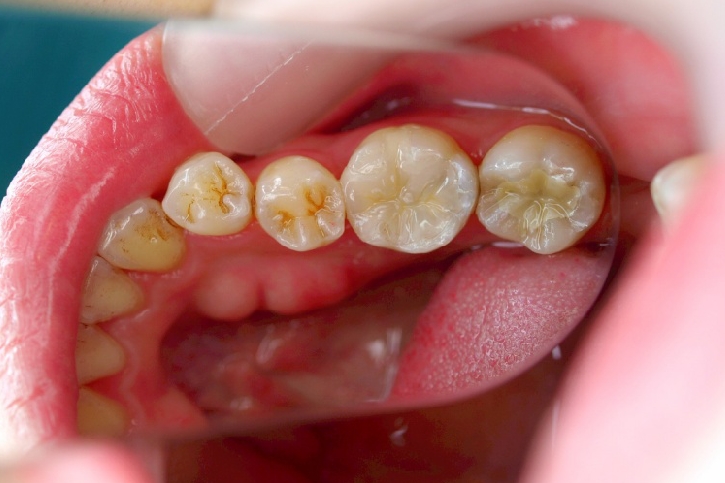

2013年3月2日千葉市中央区 S.K様 左下6番 ハイブリッドセラミックインレー修復

ハイブリッドセラミックス修復

担当歯科医師:丸林浩太郎